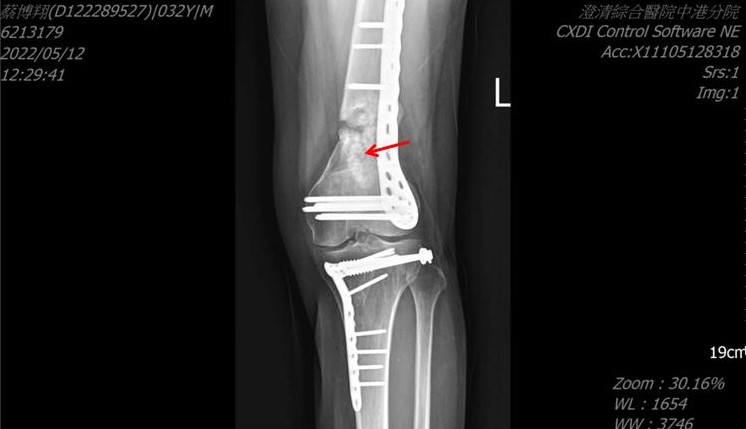

- 鋼板斷裂產生不穩定而造成的不愈合:在骨尚未癒合時鋼板不耐負重而斷裂。(圖3)

Third, the fracture of the steel plate causes instability and non-healing (Figure 3). Therefore, when injecting ACS, it is important to understand that if the steel plate is unstable, the injection failure rate will be very high. If there is fibrous tissue growth, we must remove the fibrous tissue and then inject platelet exosomes to be successful. If the plate breaks, another surgery is necessary to fix it.

(圖三) 骨內固定鋼釘斷裂造成不穩定,產生不癒合